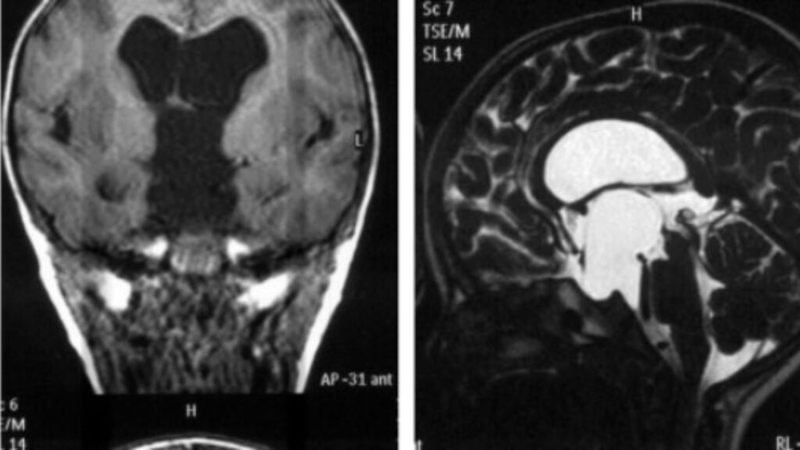

Nang màng nhện là một cấu trúc khép kín chứa dịch não tủy và có thể xuất hiện ở các vùng khác nhau của não hoặc tủy sống. Thông thường, nó không gây ra bất kỳ triệu chứng nào và được phát hiện ngẫu nhiên trong quá trình chụp cắt lớp (CT scan) hoặc cộng hưởng từ (MRI). Tuy nhiên, đôi khi nang màng nhện có thể dẫn đến các biến chứng nghiêm trọng. Nên vấn đề nang màng nhện có nguy hiểm không vẫn đang là nỗi lo của nhiều người.

Phần lớn các nang màng nhện không gây triệu chứng, không ảnh hưởng đến sức khỏe và không làm xáo trộn quá trình phát triển bình thường của não. Thường thì, nang màng nhện được phát hiện ngẫu nhiên trong quá trình chụp cắt lớp (MRI, CT scan) để chẩn đoán một bệnh lý khác như viêm xoang, đau nửa đầu chấn thương hoặc viêm xoang.